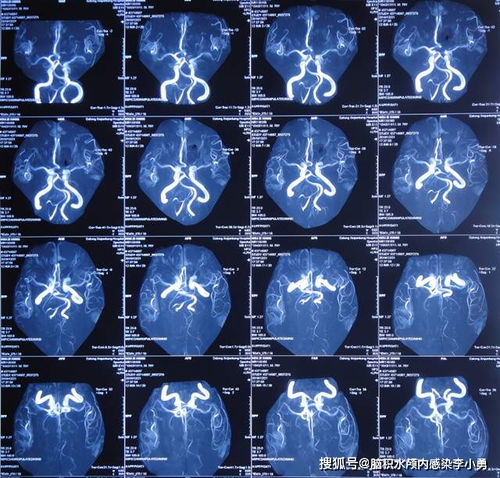

尽管现实中不存在超自然现象,但医学上的心脏移植手术已经实现。这让我们不禁思考,现实与奇幻之间的界限究竟在哪里?或许,我们每个人的内心深处都藏着一个奇幻的世界,等待着被发掘和。